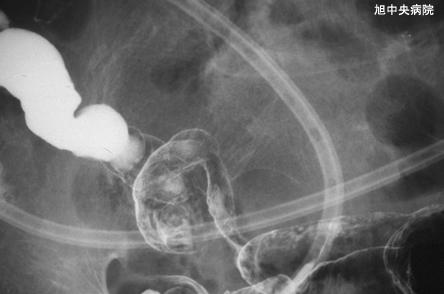

症例提示(所在地,施設名等): 千葉県・ 旭中央病院

症例登録日 2002/06/27

性別 男性

年齢 70-74

疾患(病理主体)の分類炎症性・潰瘍性疾患/虚血性腸炎

部位(臓器別)小腸/回腸

検査方法X-P

病変の最大径(ミリ)40以上